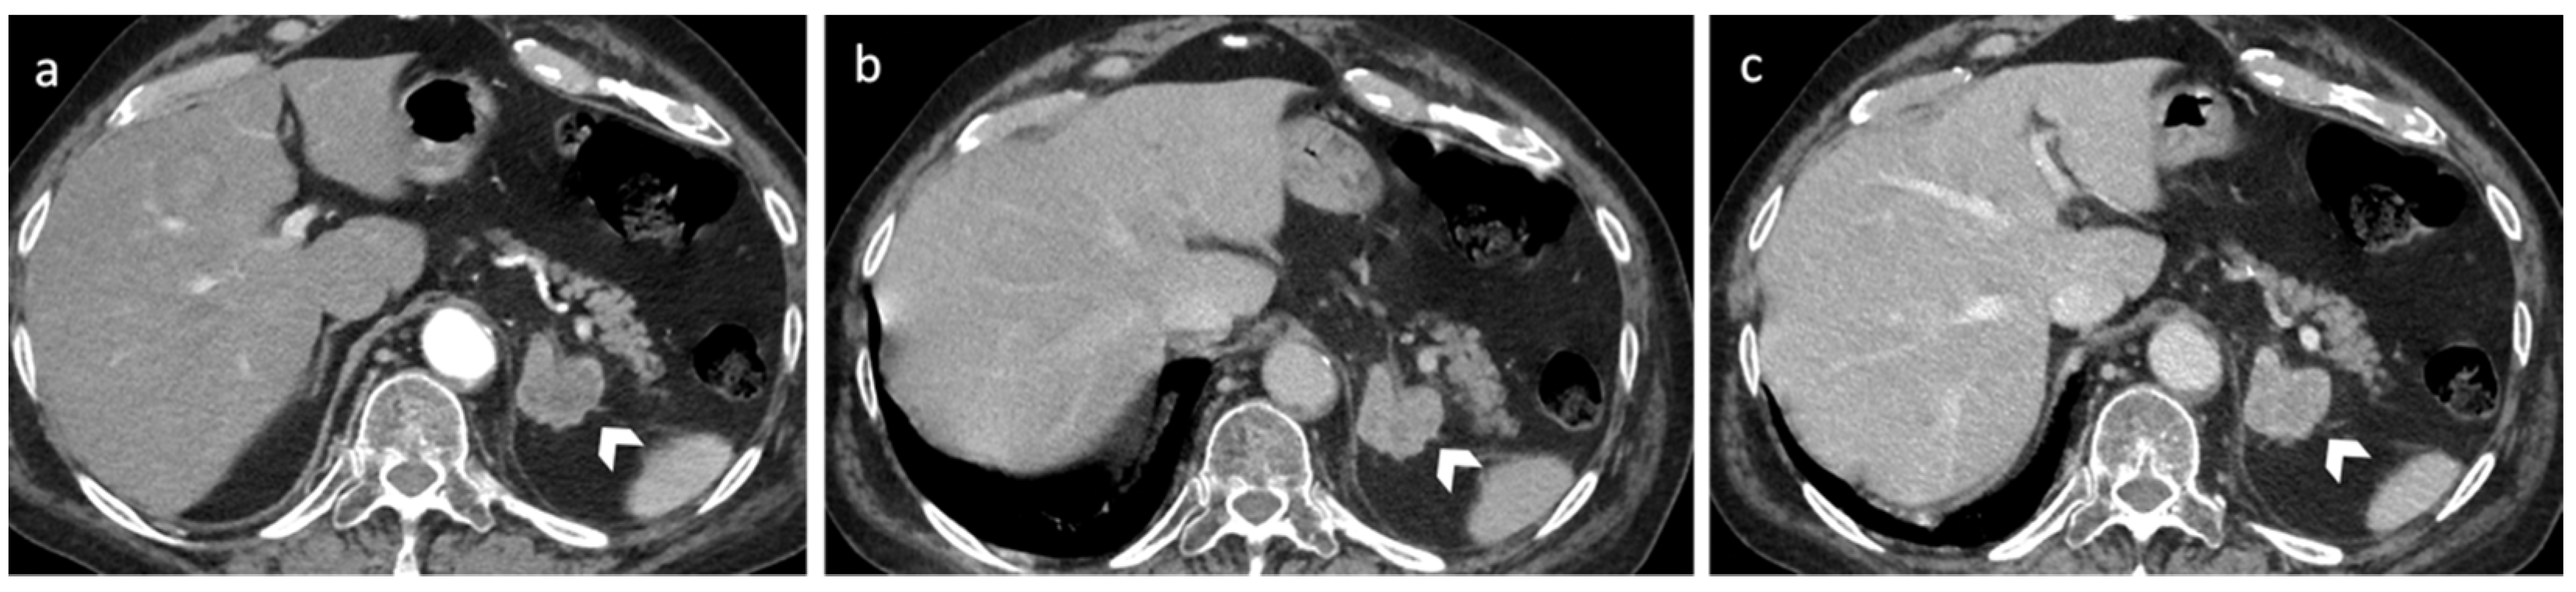

3.2. Metastasis